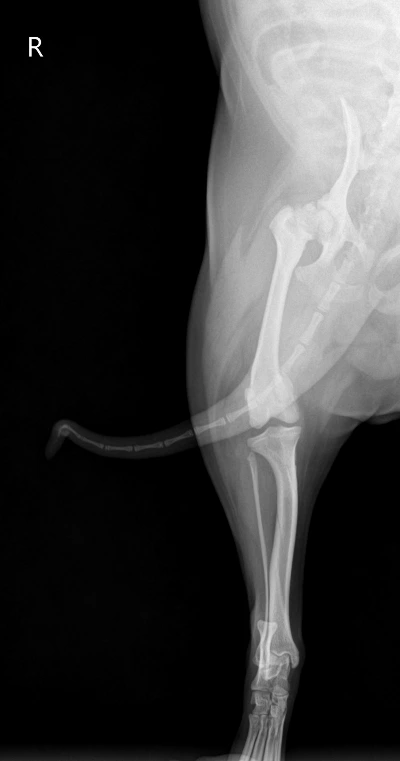

새벽 산책은 남편이 시켰다. 5시 30분에 일어나서 30분간 시키고, 나는 회사 갈 준비를 했다. 퇴근 후 밤에는 내가 산책을 시키곤 했는데, 억지로 외근을 만들어 집에 일찍 들어가려고 노력했다. 그렇게 우린 아침저녁으로 산책만 시키면 되는 줄 알았다. 푸디가 뒷다리를 잘 못쓴다는 사실을 알면서도 병원에 데려가기가 무서웠다. 수술하라고 할까 봐. 중성화 때도 얼마나 마음이 아팠는데, 또 몸에 칼을 대게 하긴 싫었다. 그래서 그냥 모른 척하고 있었는지도 모른다. 그러던 어느 날, 푸디가 정말 뒷다리를 절뚝거리며 걸었다. 가끔 낑낑대기도 하면서, 안 되겠다 싶어서 바로 병원에 갔는데, 수의사는 대퇴골두(엉덩이뼈) 쪽에 이상이 생겼다고 했다. 수술이 불가피하다고 빠른 시일 안에 수술을 하는 것이 좋겠다고 말했다. 혹시나 하는 마음으로 다른 병원에도 가봤지만, 똑같은 말만 반복했다. 하늘이 무너지는 것 같았다. 대퇴골두와 뒷다리 뼈가 연결이 자연스럽게 이어져야 하는데 푸디는 어떤 이유 때문인지 튀어나와 있었다.

엑스레이상에서도 오른쪽과 왼쪽 뒷다리에는 확연한 차이가 있었다. 엉덩이와 뒷다리 뼈가 이어지는 부분에 이미 뼈가 끊어져 알 수 없는 구조물이 붙은 게 보였다. 수술방법은 뼈를 절단하는 것이었다. 사람의 경우는 뼈 대신에 인공 구조물을 넣지만, 강아지는 그냥 절단한 채로도 괜찮단다. 대신 수술 후 케어가 필수적이라고 했다. 뒷다리 한쪽을 쓰지 않으려고 하면 퇴화될 수 있어서 무조건 운동을 시켜야 한다는 것이다. 이것저것 생각할 것도 없었다. 2022년 1월 27일, 푸디 수술 이후 난 직장을 나가지 않고 강아지 돌보는데 전념했다.